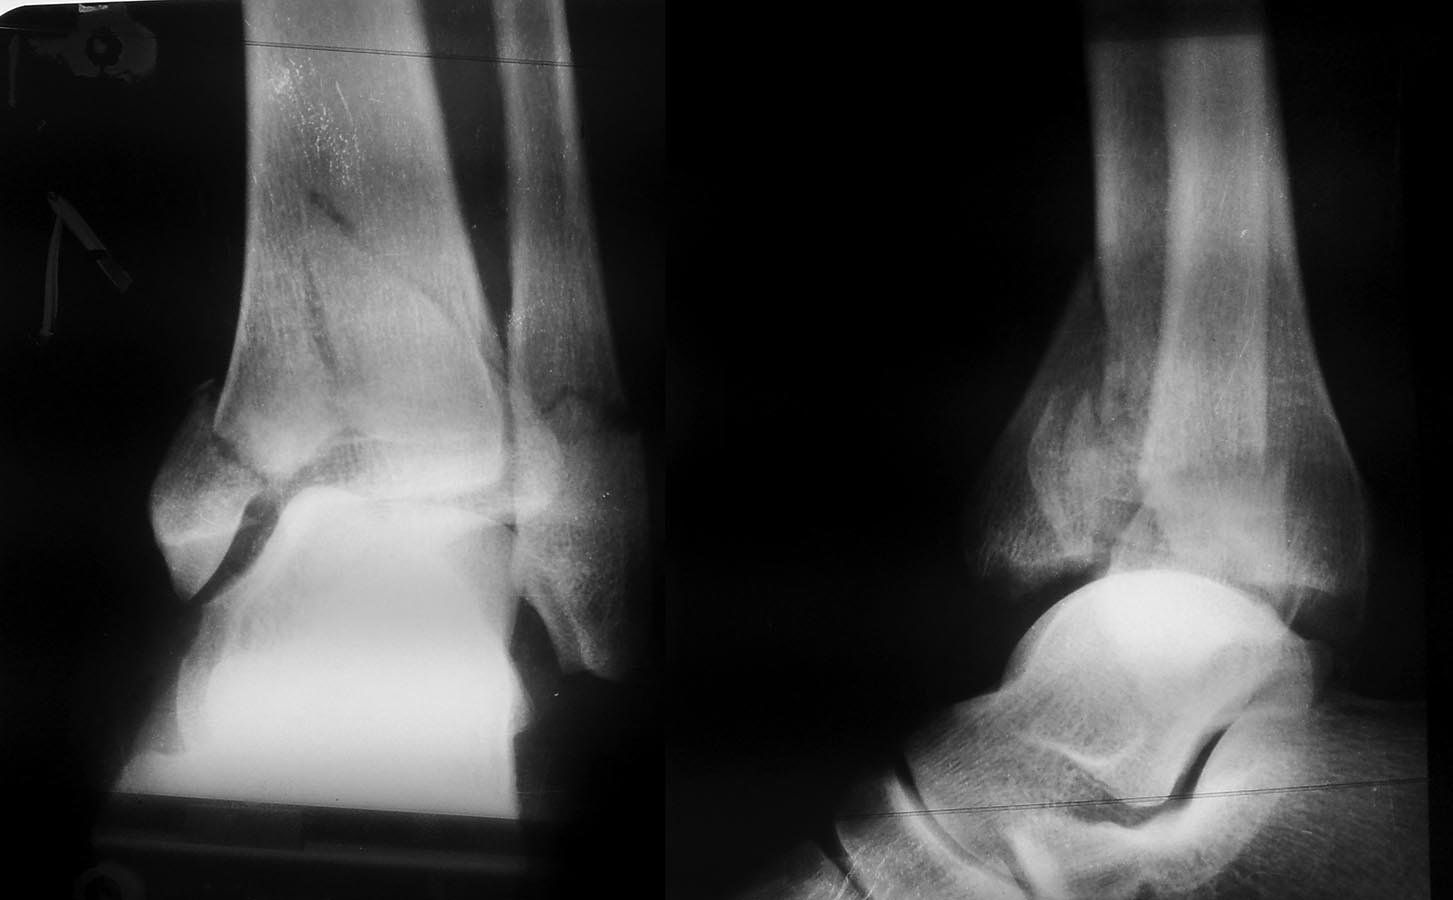

Вот снимок до операции. Почему-то прошлый раз не загрузился.